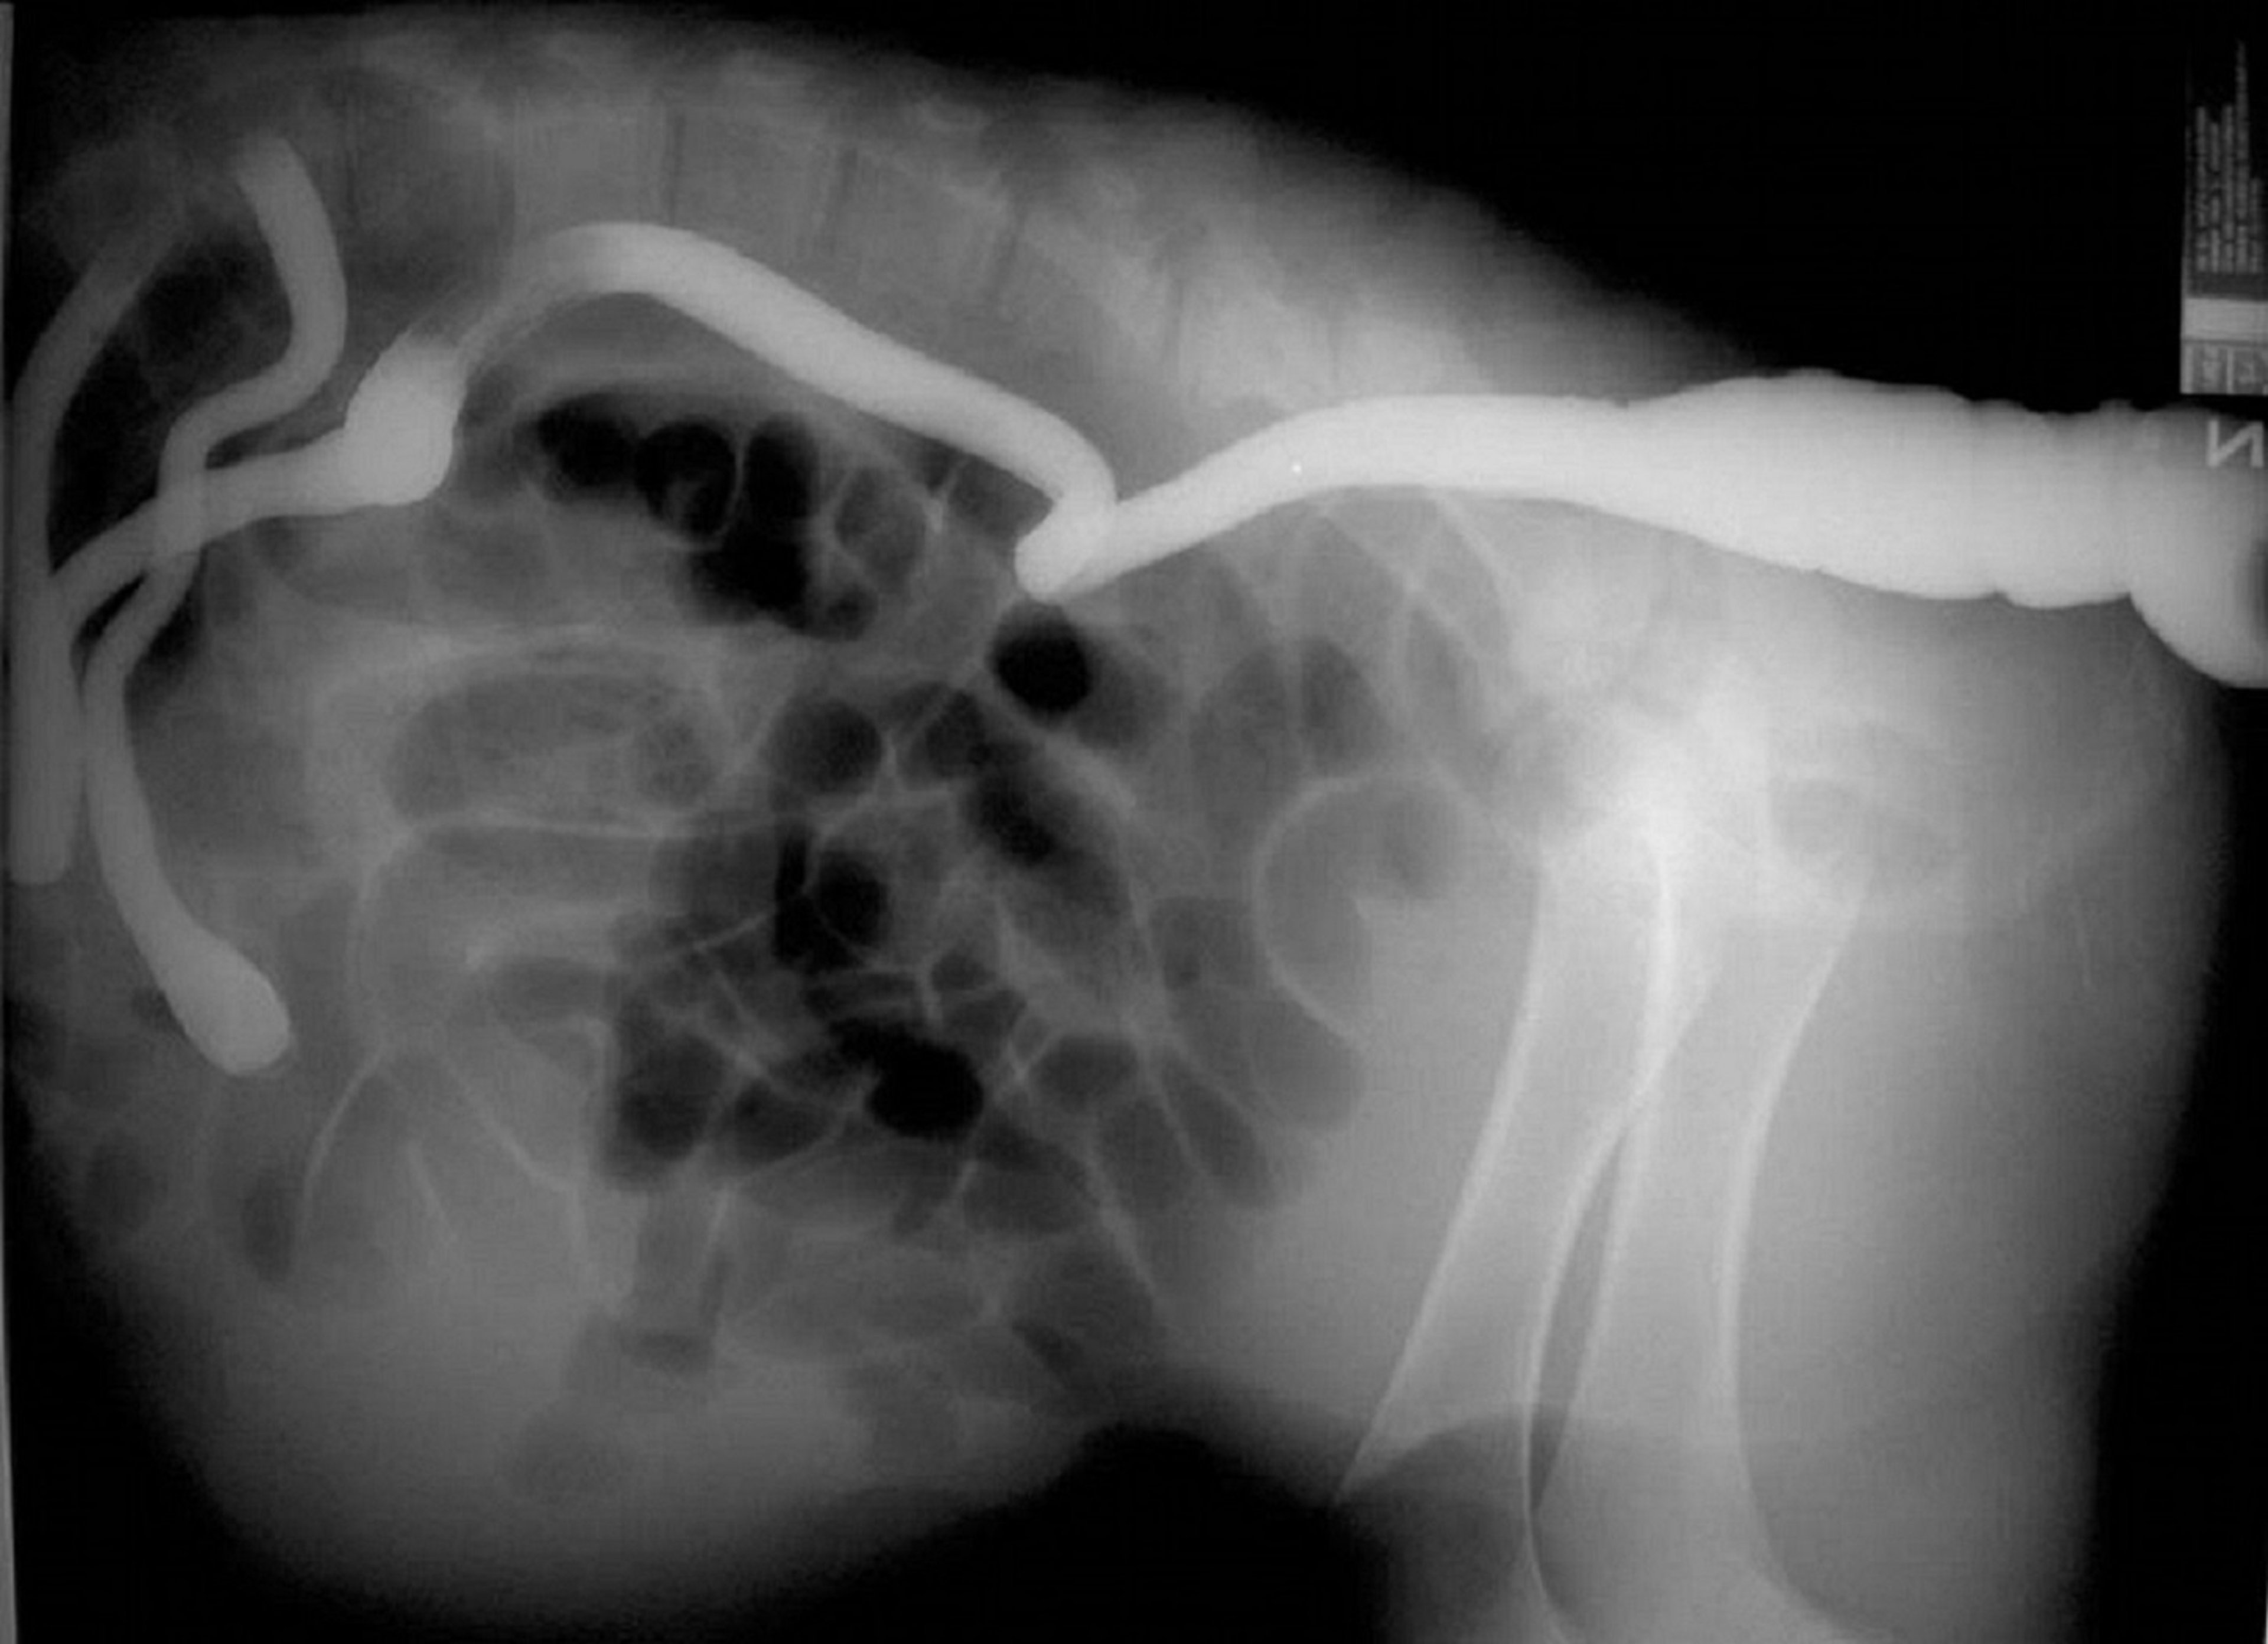

This lateral radiograph (with contrast) shows atresia coli in a calf. Contrast material has been administered rectally and continues orally only to the colon, where it stops in a blind end.

Courtesy of Dr. Sameeh M. Abutarbush.